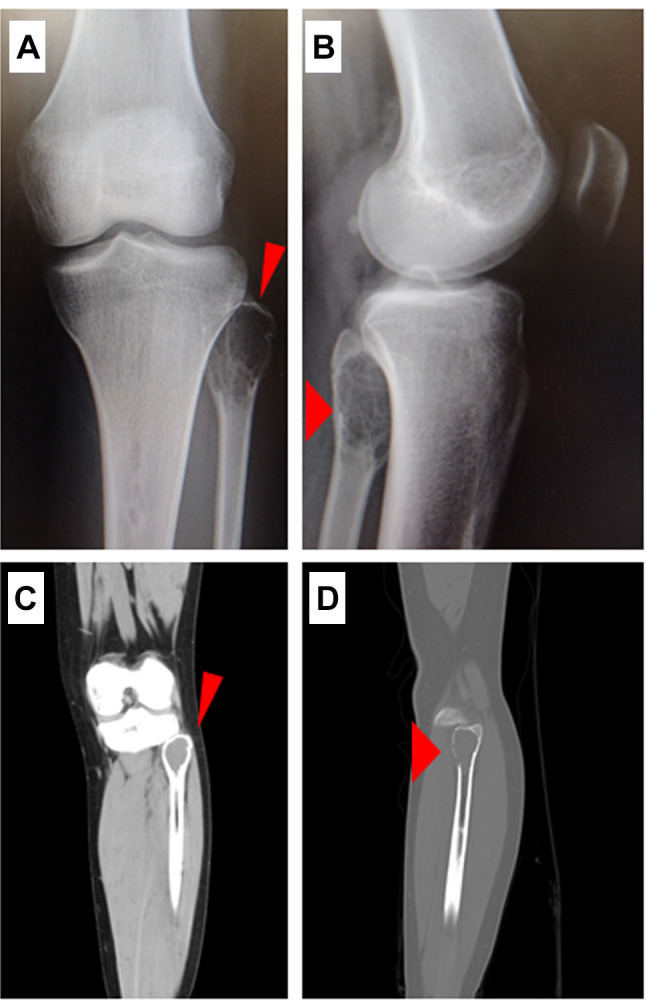

Case report: A 15-year-old female presented to a primary care physician with pain in the lateral aspect of the left knee and was referred to our department with a suspected bone tumor owing to radiographic findings of osteolysis of the proximal fibula. Computed tomography indicated osteolysis of the proximal fibula, and the bone cortex was thin and partially irregular. Magnetic resonance imaging indicated a mass in the same area, with hyperintense changes in both T1- and T2-weighted images. No biopsy was performed; however, bone tumor curettage and artificial bone grafting were performed. The final pathological examination indicated osteoclastic, multinucleated giant cells. No malignant findings were observed, and the patient was diagnosed with GCTB. No recurrence was observed one year after surgery.